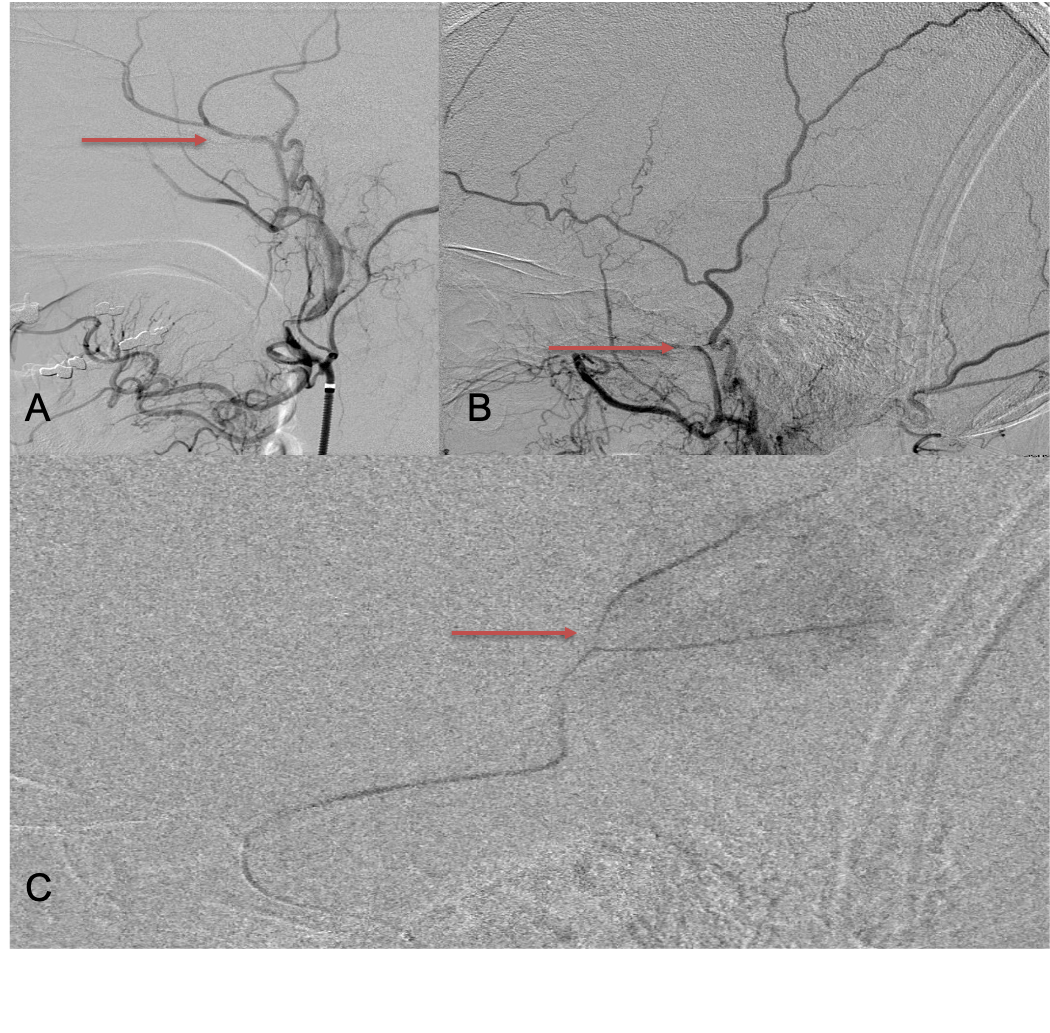

The patient agreed to receive minimally invasive treatment with Bilateral Middle Meningeal Artery Embolization, a new approach to promote resorption of chronic and subacute subdural hematomas in patients that are not improving with conservative measures or have contra-indications to surgical evacuation. Selective catheterization of the Middle Meningeal Artery is followed by transarterial embolization of the territory and inflammatory membranes that are felt to be secreting serosanguinous proteinaceous exceeding the capacity for resorption. MMA embolization was performed bilaterally in this patient. (Figure 2. A and B)

Figure 2. A) Initial right ECA angiogram ; B) Post MMA Embolization; C) Selective Embolization Of Middle Meningeal Artery Membranes using PVA particles (arrows)